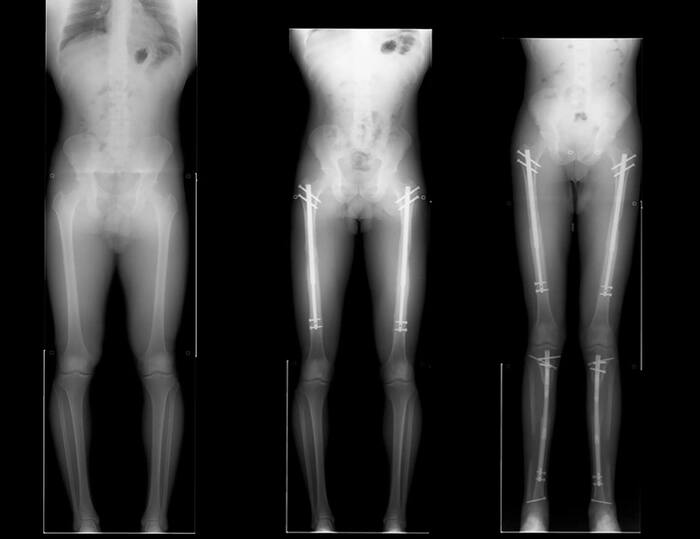

Принцип работы прост: тебе ломают кости и вставляют металлические иглы, которые потом удлиняют с помощью магнита. Вырасти можно до 15 сантиметров, а стоимость процедуры от 70 тыс до 150 тыс баксов.